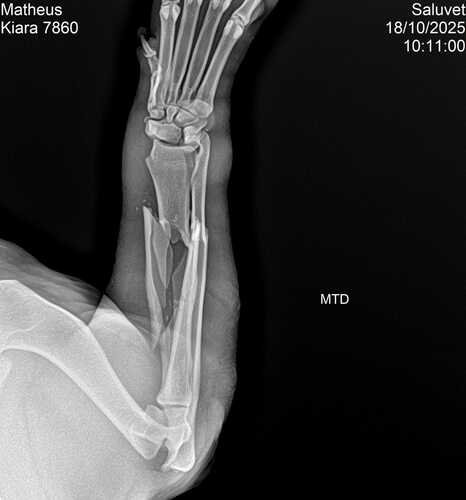

Olá boa noite me chamo Matheus tenho um casal de pet da raça pitbull e infelizmente recente na sexta feira ele tiveram uma briga feia na qual meu cachorro macho Zeus quebrou a pata da kiara e desde então estou atrás de ajuda ONGs ou até mesmo clínica mais em conta só que até agora os valores saíram completamente do meu orçamento amo meus cães e não desejo isso a ninguém ver a situação e infelizmente não poder solucionar o problema mas estou vindo através das redes sociais pedir a ajuda que vcs com qualquer quantia que tocar no coração de cada um a cirurgia dela tem que ser feita por um médico ortopedista e os valores não são baratos mas com a ajuda e colaboração de todos creio que dará certo no momento estou tratando dela apenas com antibióticos

Quem sentir no coração e quiser conhecer o caso mais a fundo tenho o raio X e mando fotos ou vídeos de como ela se encontra no momento obrigado